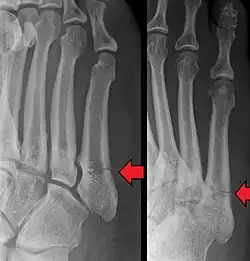

- Proximal diaphysis, typically stress fracture.[12][13]

- Metaphysis: Jones fracture[14]

-Tuberosity: Pseudo-Jones fracture[15] (avulsion fracture).[15]

Other proximal fifth metatarsal fractures exist, although they are not as problematic as a Jones fracture. If the fracture enters the intermetatarsal joint, it is a Jones fracture. If, however, it enters the tarsometatarsal joint, then it is likely an avulsion fracture caused by pull from the fibularis brevis tendon. An avulsion fracture at the base of the fifth metatarsal is sometimes called a "dancer's fracture" or a "pseudo Jones fracture", and usually responds readily to non-operative treatment.[18] The X-ray appearance of the developmental "apophysis" in this area may have some resemblance of a fracture, but is not a fracture; it is the secondary ossification center of the metatarsal bone. It is a normal finding that occurs at this site in adolescents.[19] If an injury to that area has occurred, the physician is often able to interpret certain radiographic clues to make the differentiation. An avulsion fracture at this location is typically extra-articular and oriented transversally as compared to the longitudinal orientation of an unfused apophysis.[19]